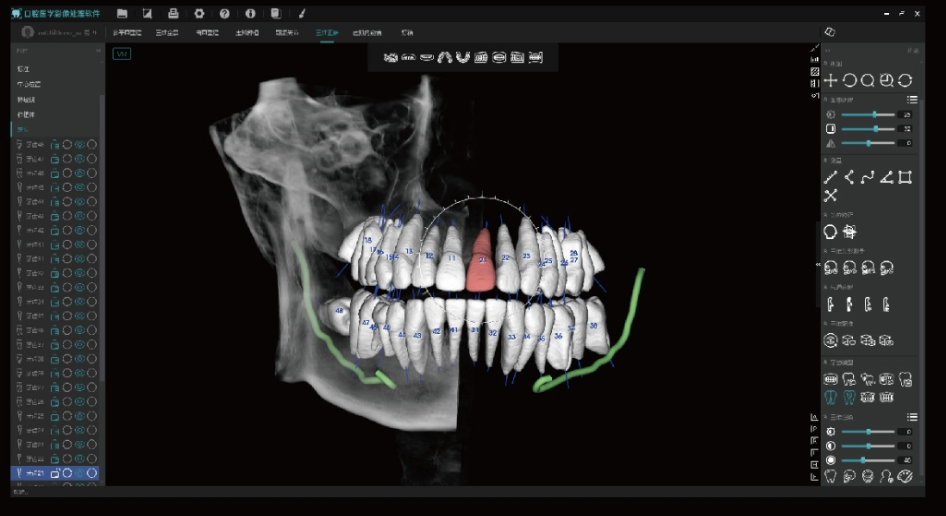

Tecnologia Inovadora Root-Bone Glass

Suporta o posicionamento manual dos dentes, a remoção dentária e a observação tridimensional da câmara pulpar.

Permite o planeamento imediato de extrações e implantes.

Sistema Ortodôntico Inteligente

Traçado Automático de Pontos de Referência

disponibiliza 68 pontos de referência e 192 itens de medição.

Suporte a Métodos de Análise Profissional:

auxilia os clínicos na análise quantitativa e na simulação diagnóstica.

Análise Inteligente Local:

funciona offline, sem necessidade de ligação à internet.